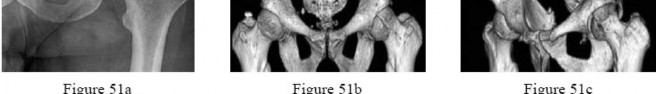

A 31-year-old man sustained an unstable closed left posterior hip dislocation in a motorcycle accident. A postreduction radiograph is shown in Figure 51a. 3-D CT scans are shown in Figures 51b and 51c. What is the optimal surgical approach that will allow for the most appropriate treatment?